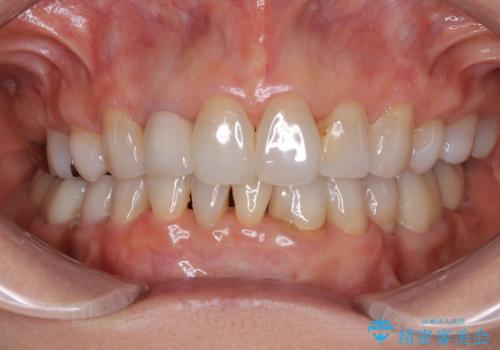

- 奥歯の目立つ銀歯と、神経が失活して変色した前歯を気にして来院された患者様です。

銀歯と歯の間に隙間があり、冷たいものがしみる知覚過敏の症状が認められたため、銀歯を白くするだけでなく、知覚過敏症状の改善も狙って補綴治療を行うこととしました。

長年口を開ける度に気になっていた銀歯が一気に自然な色合いとなり、患者様には大変満足していただけました。